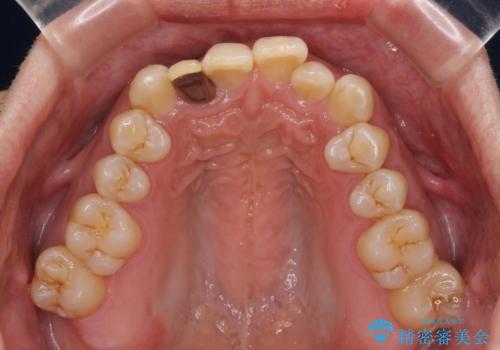

前歯のデコボコを治したい インビザラインによる矯正治療

- 前歯のデコボコを気にして来院された患者様です。

目立たない装置で手軽に治したいとのことで、インビザラインにて矯正治療を行うこととしました。

前歯のクラウンは変色が著しいため、矯正治療後にオールセラミッククラウンにて補綴治療を行うこととしました。

担当医としてはもう少し前歯のデコボコを改善したいところでしたが、患者様としては十分に満足いく歯列であり、マウスピース矯正に飽きてしまったとのことで、治療終了となりました。